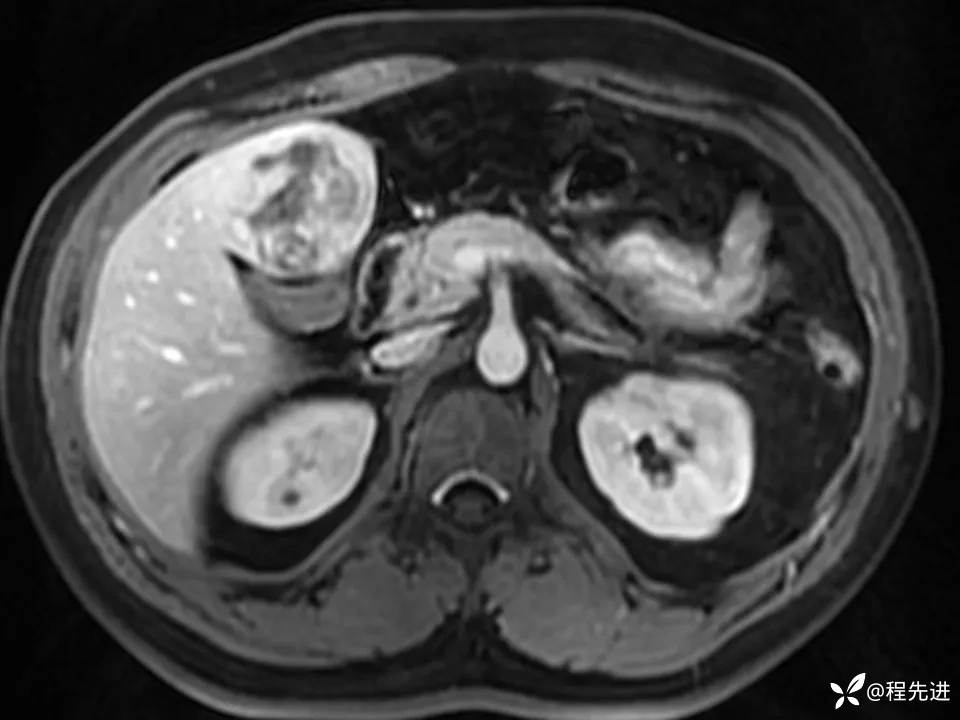

患者性别:男

患者年龄:27岁

简要病史:体检发现肝脏占位2周

既往史:平素体健,无特殊

实验室检查:(-)